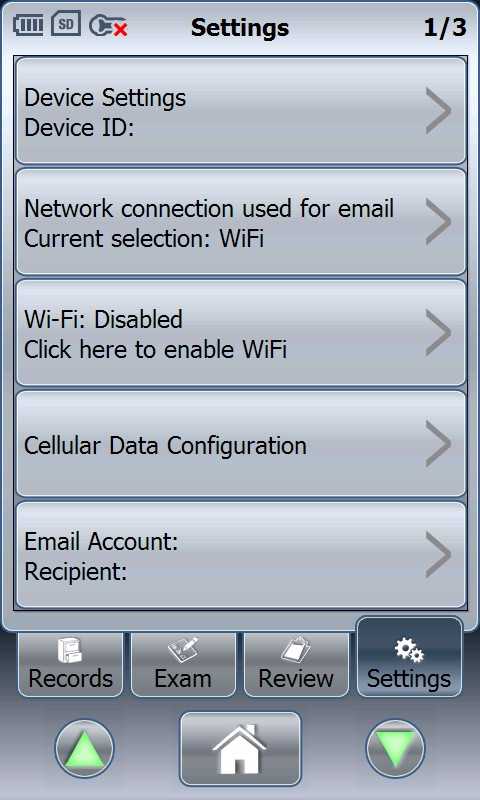

Εικόνες με το MobiUS SP1 μπορούν να σταλούν σε άλλον γιατρό ενώ μια νοσοκομειακή μονάδα θα ετοιμαστεί πιο άμεσα για να παραλάβει τον ασθενή.